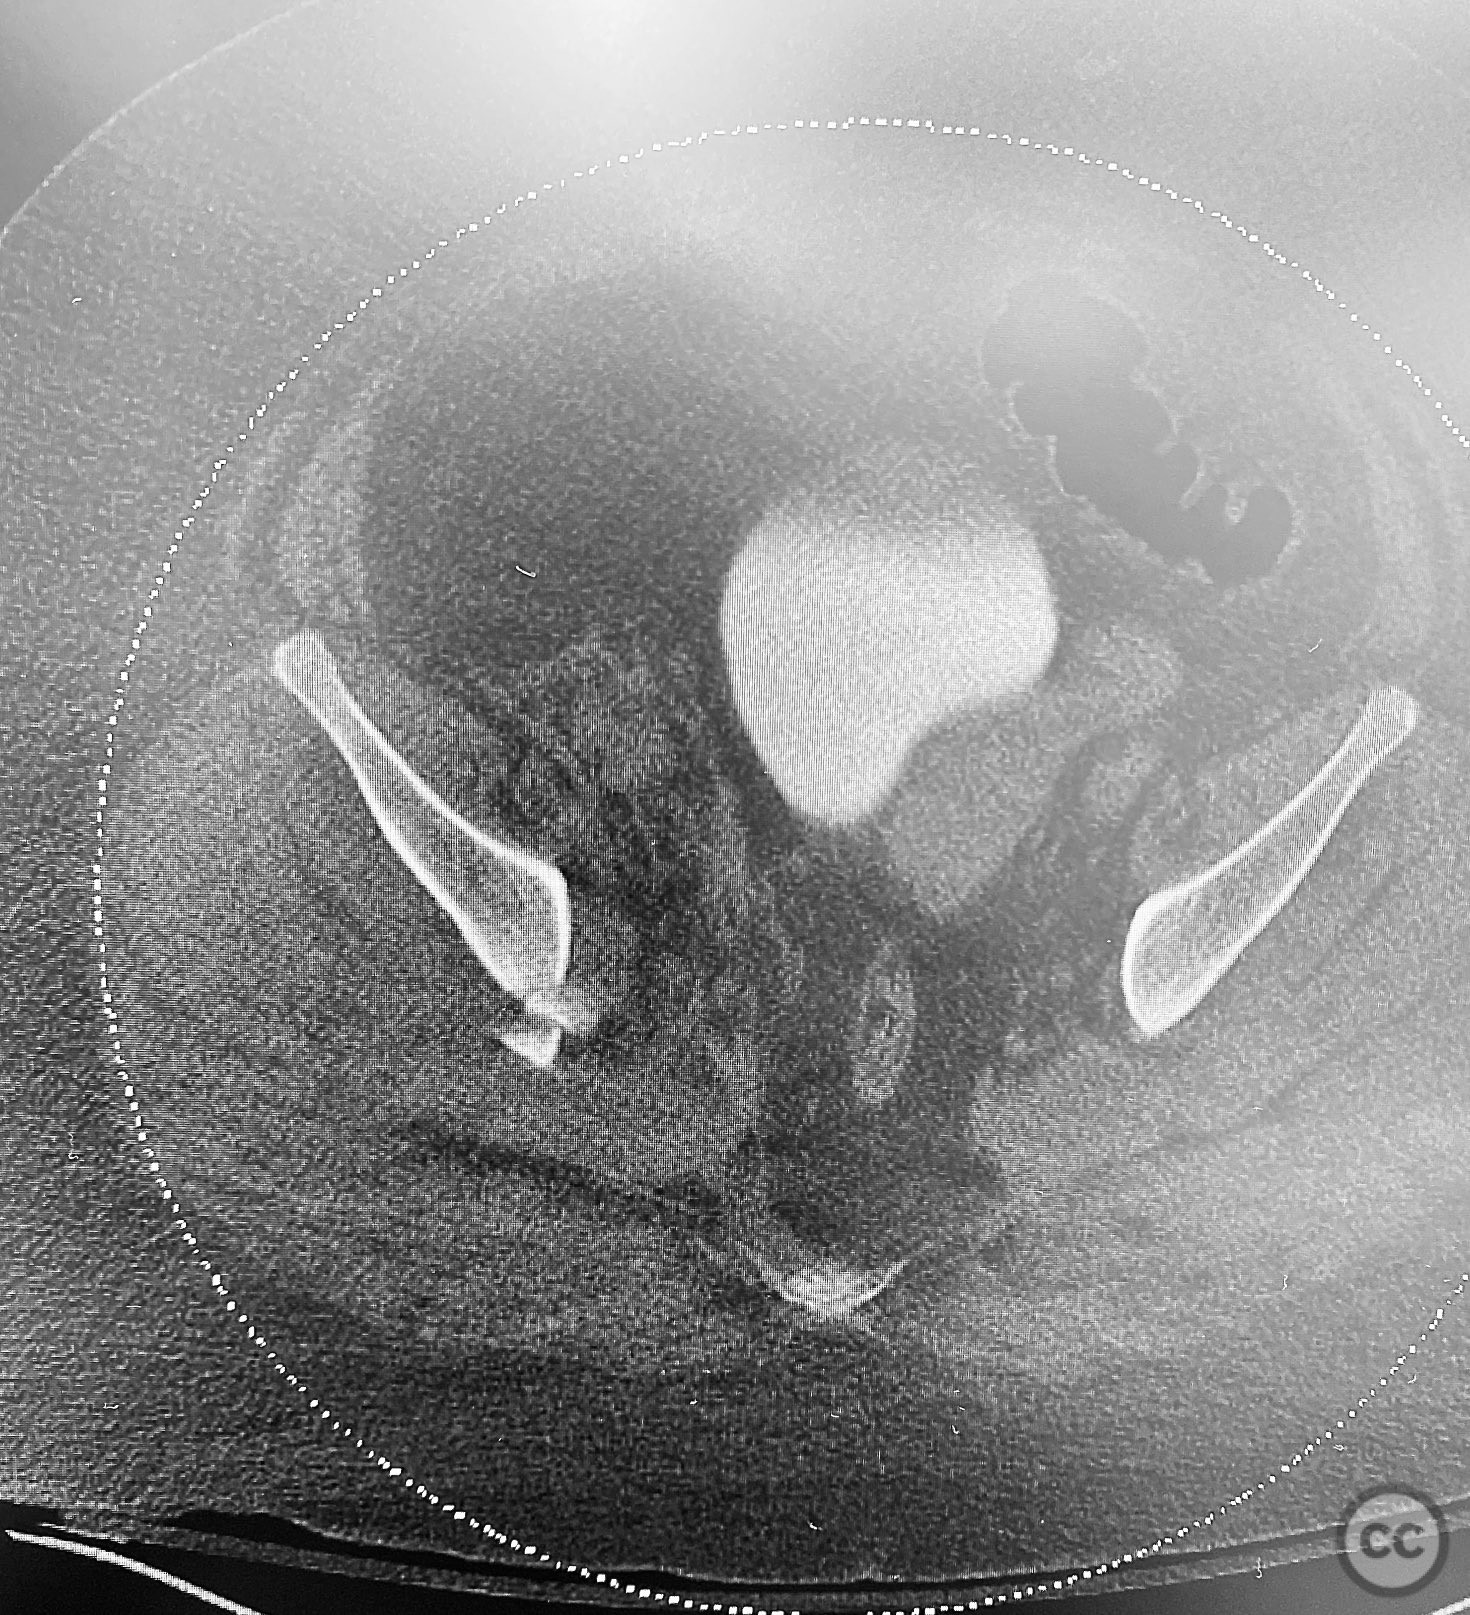

Clinical and radiological findings:  The patient is morbidly obese and sustained an unstable, displaced posterior column/posterior wall (PC/PW) acetabular fracture. Axial computed tomography images revealed a 2x2x1.5 cm pyramidal chondrocancellous articular fragment wedged in the fracture plane near the incisura ischiadica major (greater sciatic notch). Surface-rendered reconstructions further delineated the fracture morphology and fragment position. Obesity was noted to complicate all aspects of management, including anatomical localization, intraoperative imaging, and soft tissue handling.